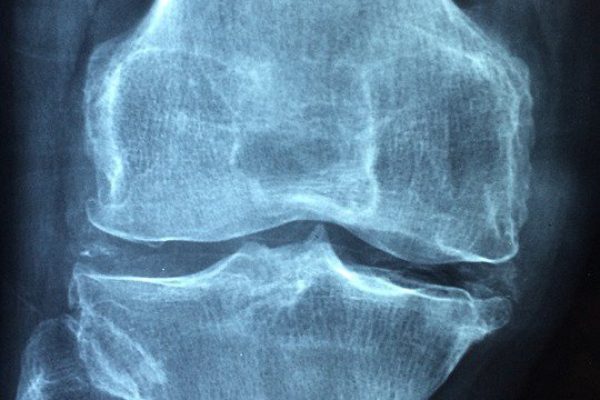

ROMA – Dopo i 70 anni, una donna europea su due andrà incontro a una frattura ossea legata all’osteoporosi. Il 66% delle donne e il 50% degli uomini sono colpiti da osteoporosi e osteopenia (condizione in cui la massa ossea è ridotta rispetto alla normalità che spesso precede l’osteoporosi e che espone ad un maggior rischio di frattura). Secondo l’Organizzazione mondiale della Sanità, a causa dell’osteoporosi in tutto il mondo ogni 3 secondi si verifica una frattura di femore, polso o vertebra. La frattura del femore, principale conseguenza della patologia, comporta una mortalità del 5% e del 20% nel mese e nell’anno successivi. Circa il 30% dei pazienti fratturati va incontro a una disabilità permanente, il 40% perde la capacità di camminare autonomamente, l’80% ha bisogno di supporto nelle attività quotidiane.

L’osteoporosi è una patologia cronica caratterizzata da una perdita della massa e della qualità dell’osso, favorita da fattori costituzionali, genetici e ambientali, come le abitudini alimentari, il consumo di alcol, tabacco e caffè, la carenza di attività fisica e l’assunzione di farmaci che interferiscono con il normale metabolismo di fosforo e calcio.

Negli Stati Uniti e nell’Unione Europea sono affette da osteoporosi circa il 30% delle donne in post menopausa e si stima che di queste più del 40% riporterà una frattura nel corso della propria vita. In Italia vengono stimate almeno 3,5 milioni di donne con osteoporosi e più del 75% della popolazione femminile sopra i 60 anni di età soffrirebbe di fragilità ossea con aumento del rischio di fratture, che rappresentano una importante causa di disabilità, specie tra le persone anziane.Ogni anno si registrano circa 8mila ricoveri per fratture di femore in persone con oltre 65 anni.